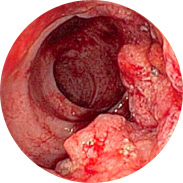

Vnetje in suppuracija rektalne sluznice

Krvavitev lahko vodi do razvoja anemije

In najhuje je rak danke!Obsežna klinična študija Hemorena je bila izvedena v Kliničnem centru (Ljubljana) leta 2016. Skupaj je v študiji sodelovalo več kot 1000 moških in žensk z različnimi stopnjami hemoroidov. Vsi preiskovanci so 3 tedne uporabljali kremo Hemoren. Rezultati študije so osupnili celo zdravnike!